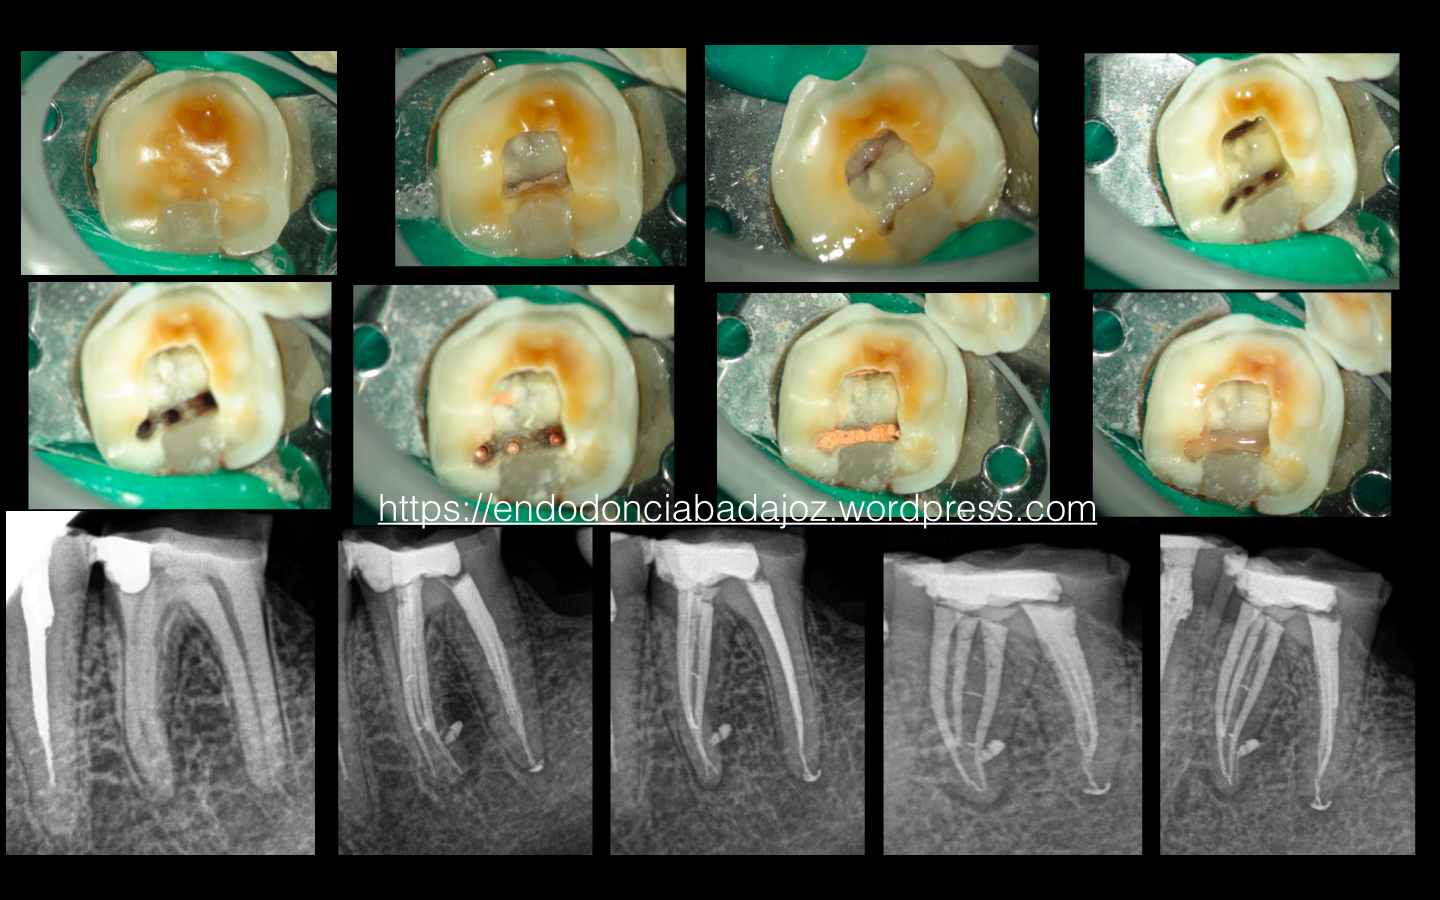

Cuidado con los istmos!!!

Es el caso de un tratamiento de un 3.6 en el que peligra, en ciertas ocasiones, esos restos de tejido orgánico que podemos dejar tras la instrumentación.